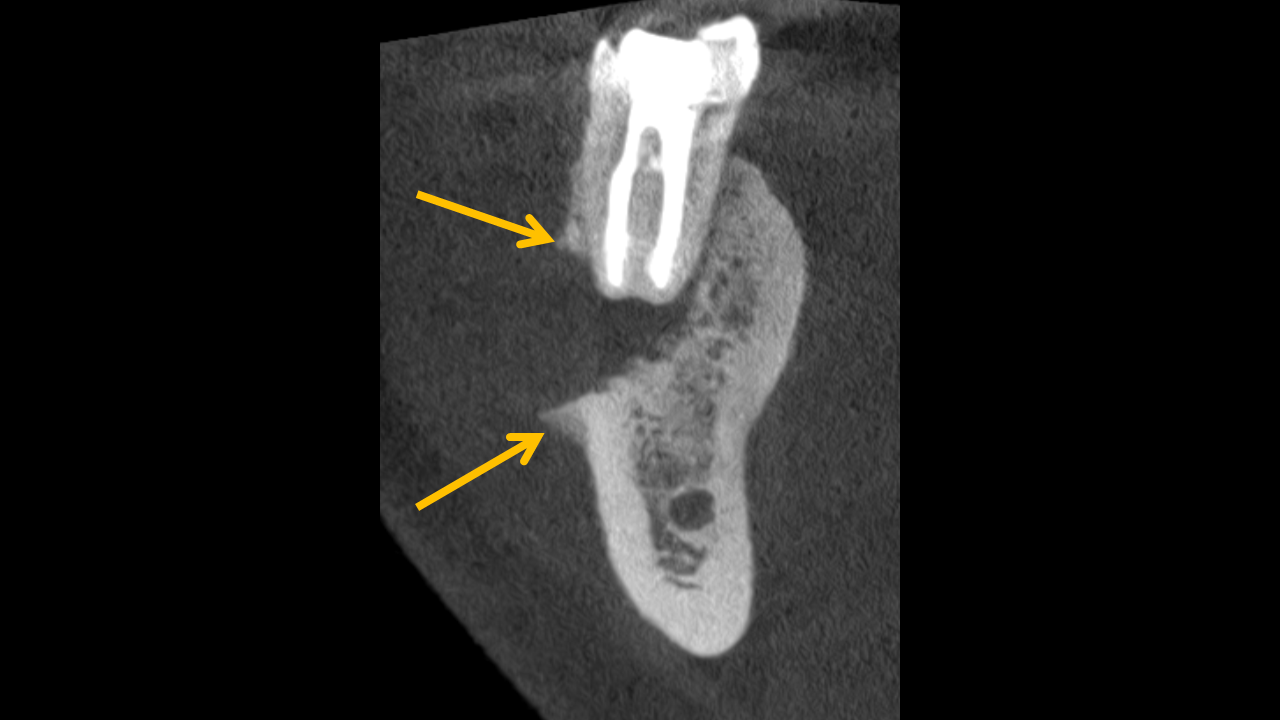

Study 2

Finding: A low-density, destructive bony lesion is associated with endodontically treated tooth #30 and has eroded the adjacent buccal cortex. Codman triangle is evident at the buccal cortex, and the surrounding trabeculation appears sclerotic. These imaging findings are suggestive of a chronic inflammatory process or malignancy.